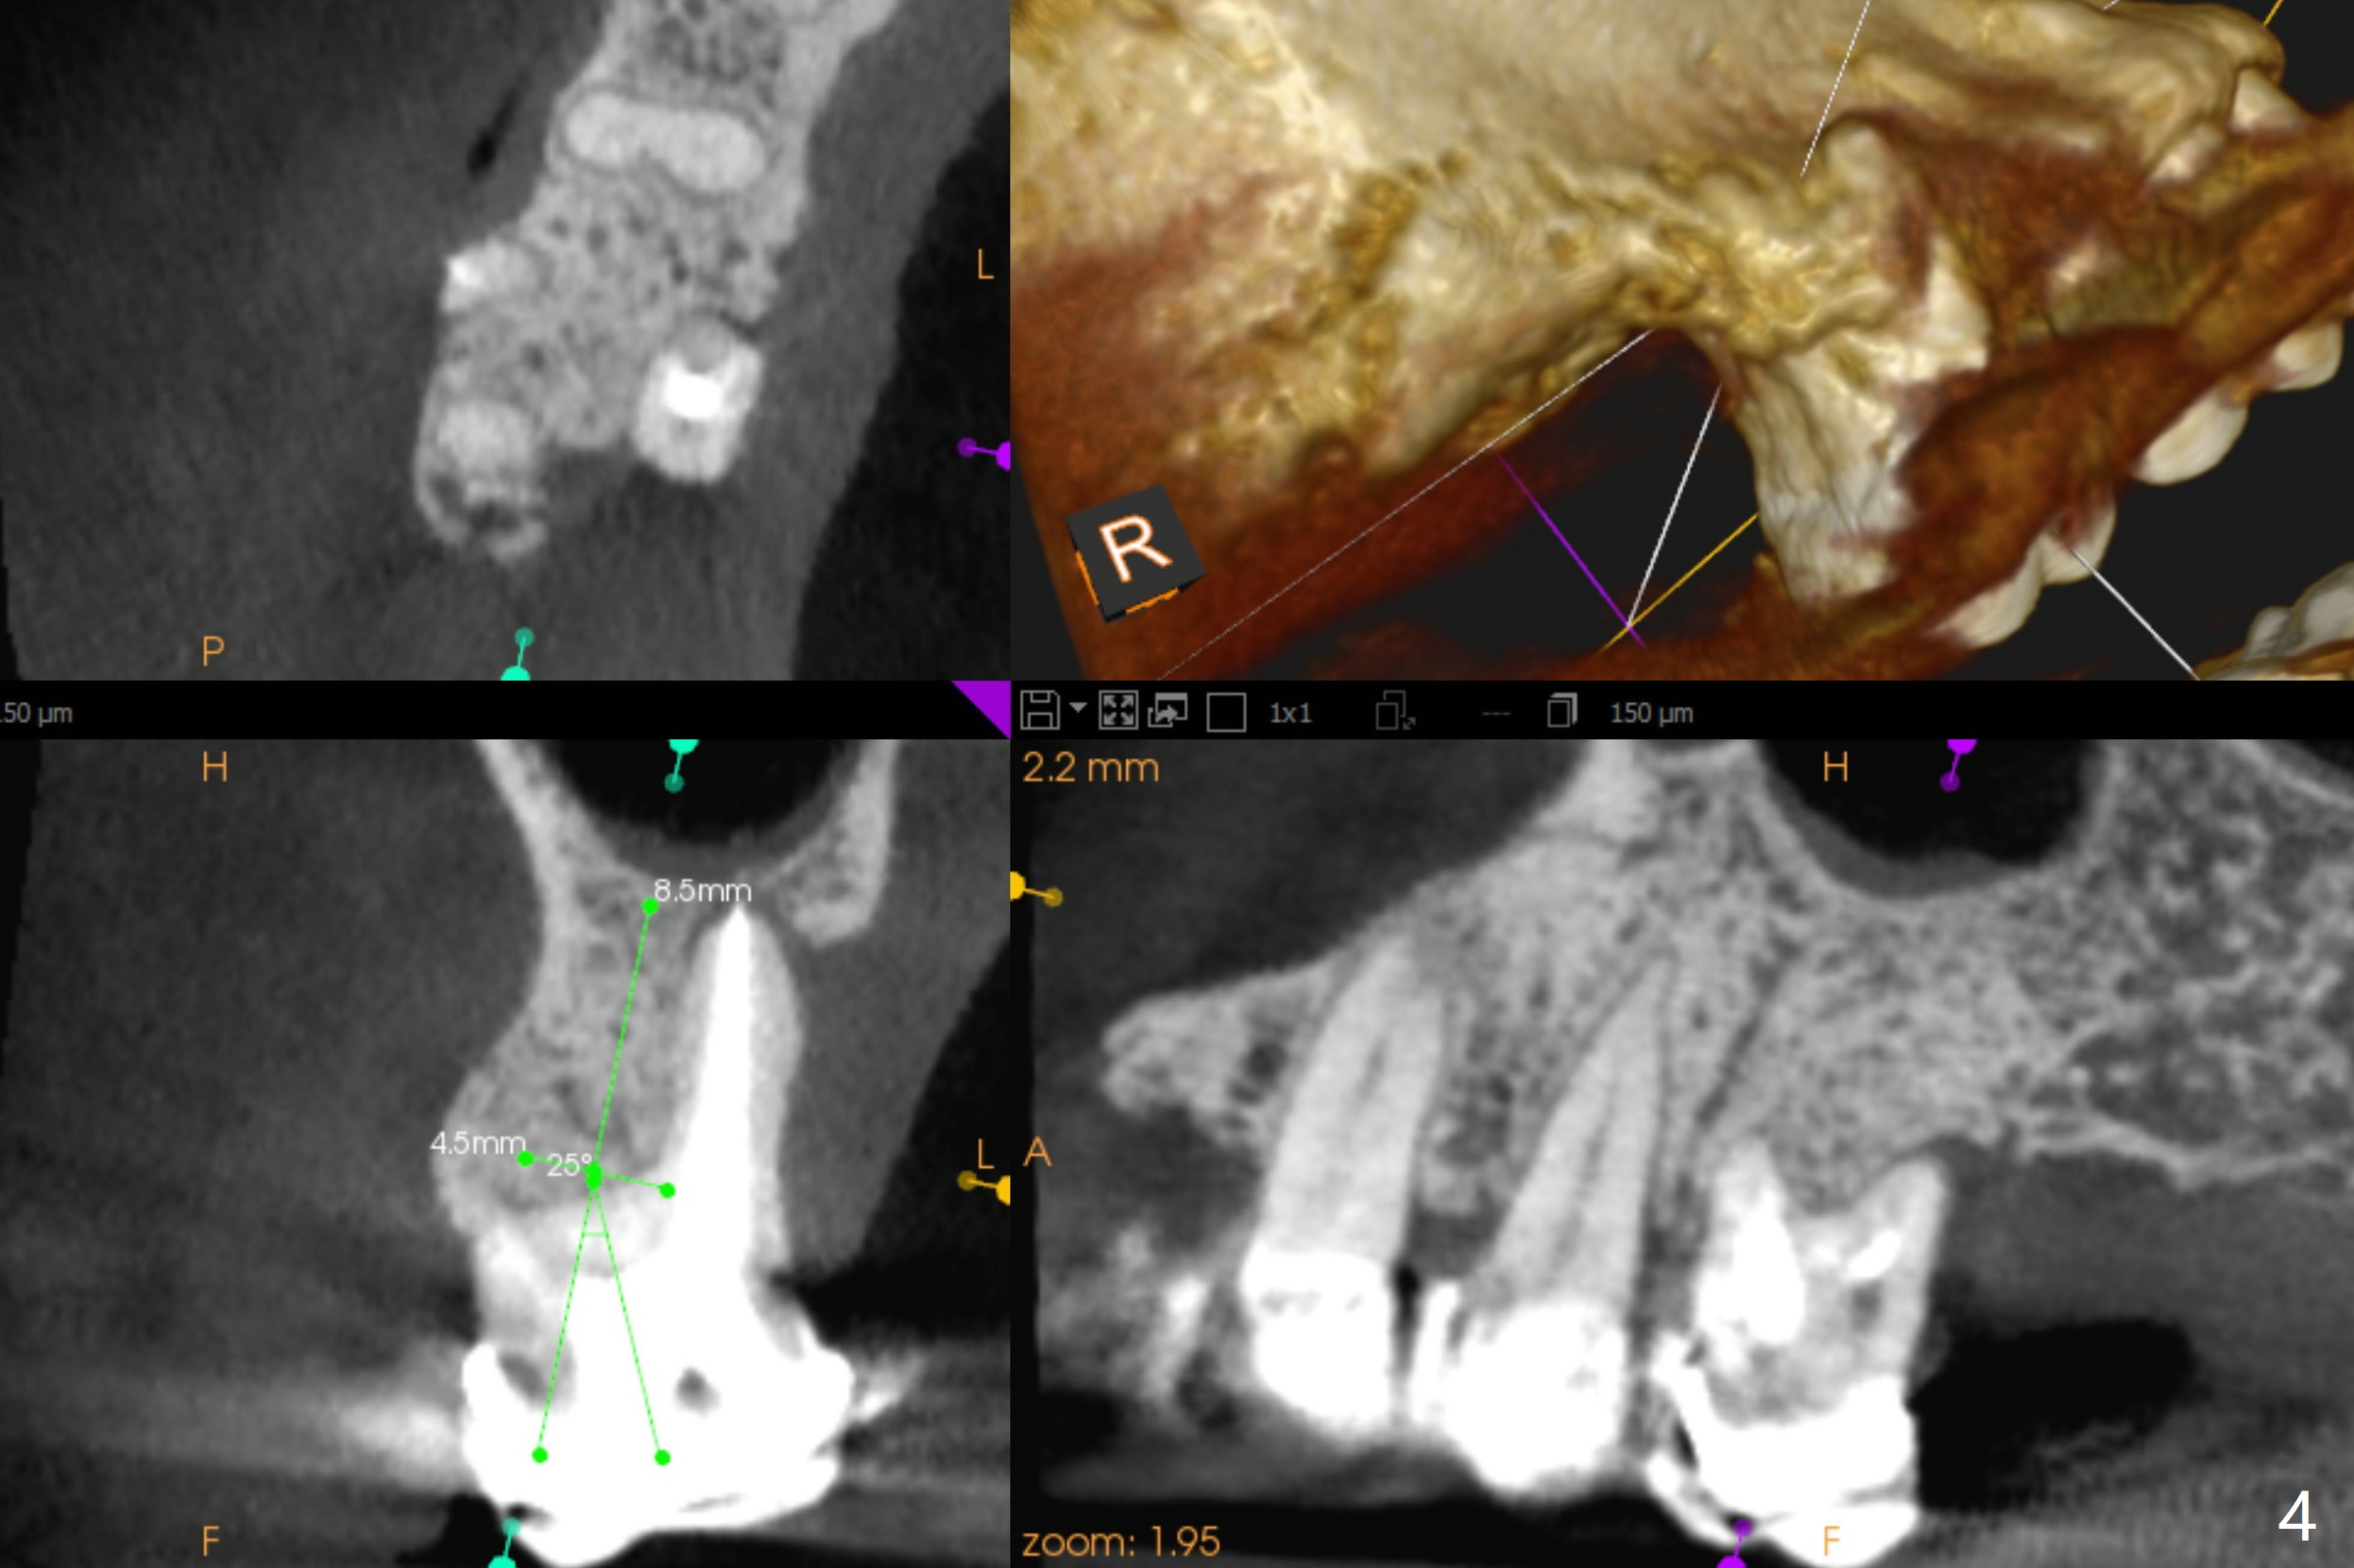

A 52-year-old woman has had chronic abscess associated with the tooth #3. The palatal root is exposed (Fig.1 P), suggesting root fracture. The apex of the mesiobuccal root seems to stick out of the buccal plate (Fig.2 *). The root canal filling is incomplete in the distobuccal root (Fig.3 *). The tooth appears to have guarded prognosis. Extraction and immediate implant is apparently a better option (Fig.4,5). It would be safer to start osteotomy in the middle of the remaining septum (Fig.6, as compared to Fig.5). After sinus lift with PRF membrane (Fig.7 yellow curved line) and implant placement (green), another piece of PRF membrane will be placed against the palatal wall of the socket, followed by bone graft (red circles) and a 25-degree angled abutment (pink).